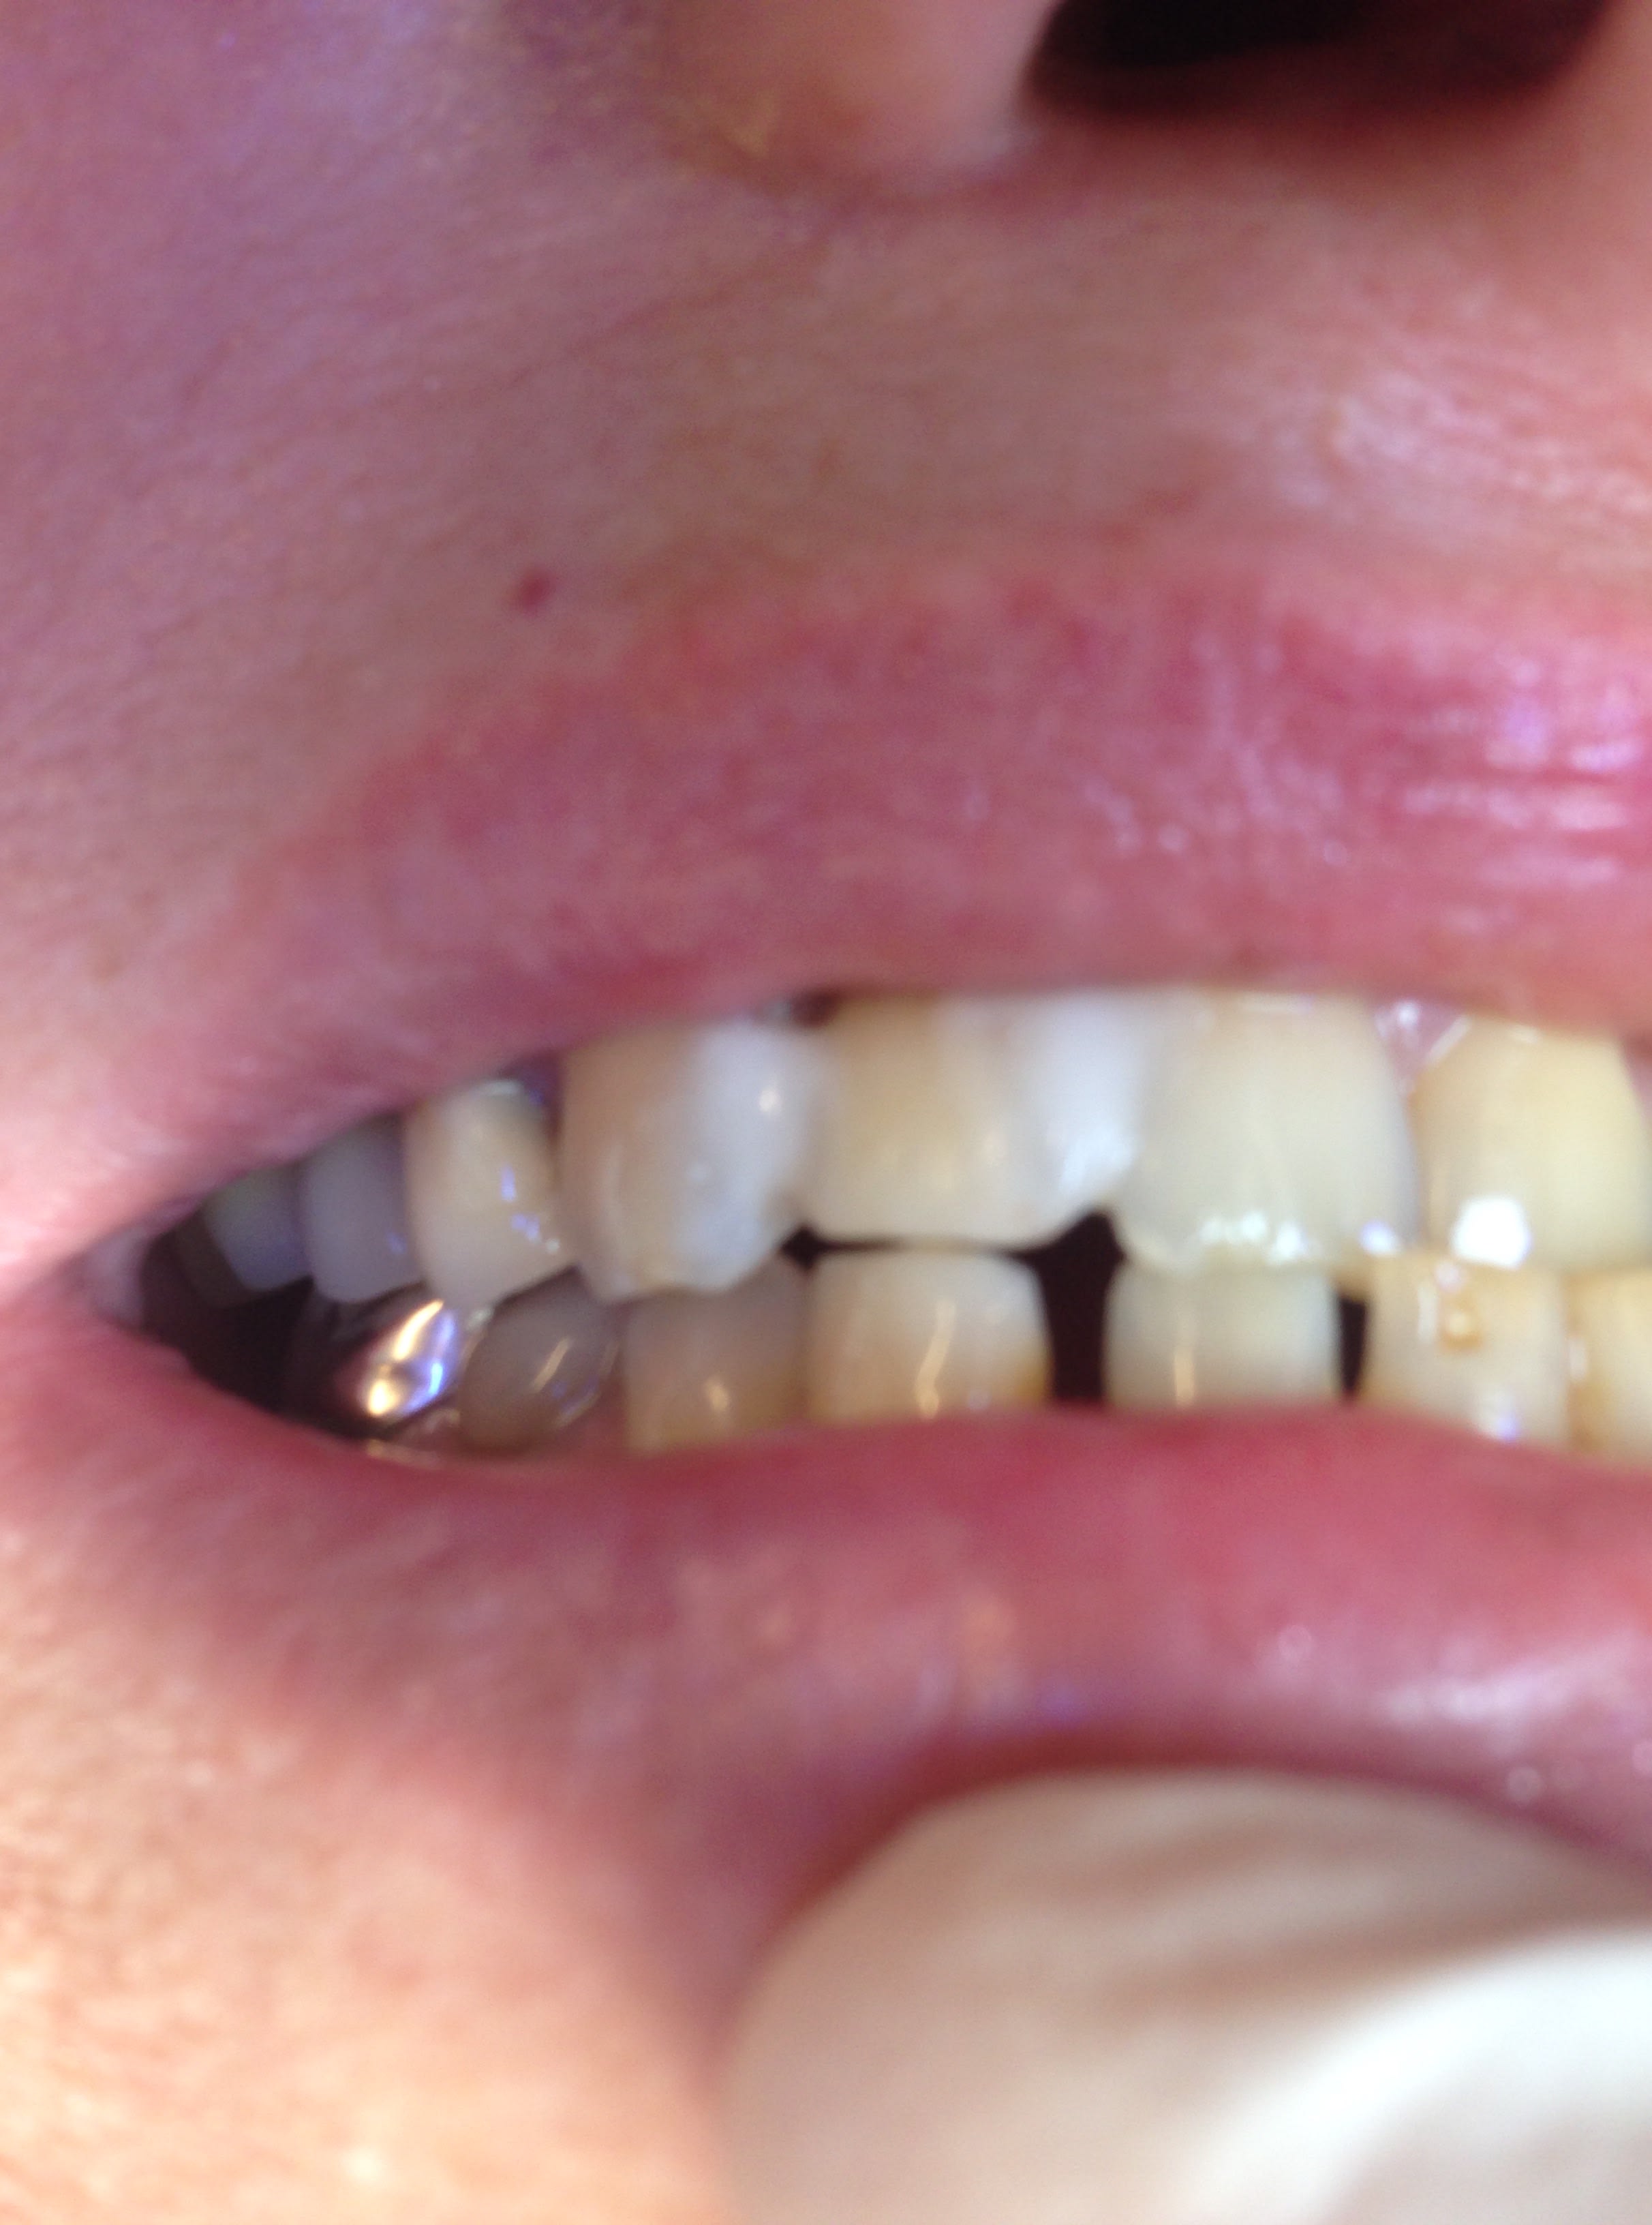

tu m'étonnes que la vis aies cassé 😊

Elle vient taper avec sa canine en plein sur sa latéral (2eme photo). Pas de dents En postérieur et articulé croisé.